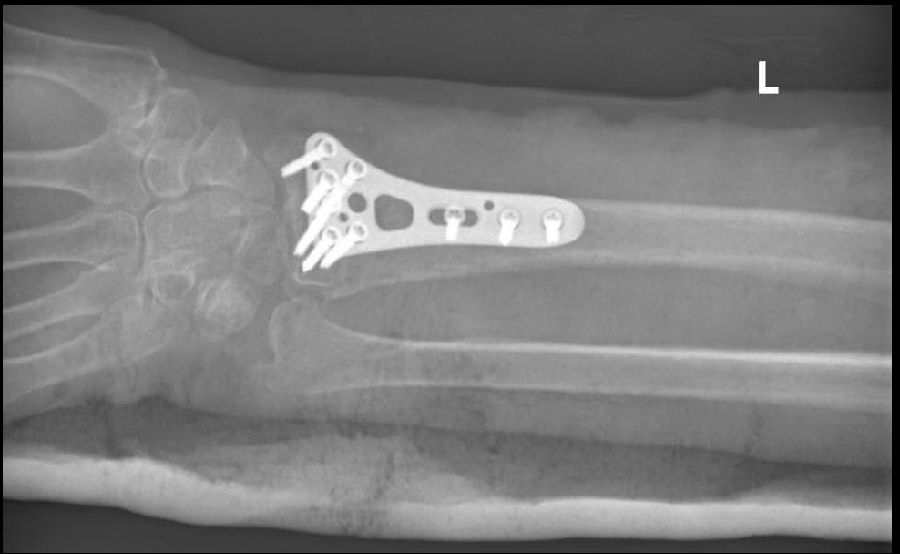

2、左桡骨远端骨折

2、左桡骨远端骨折切复内固定术